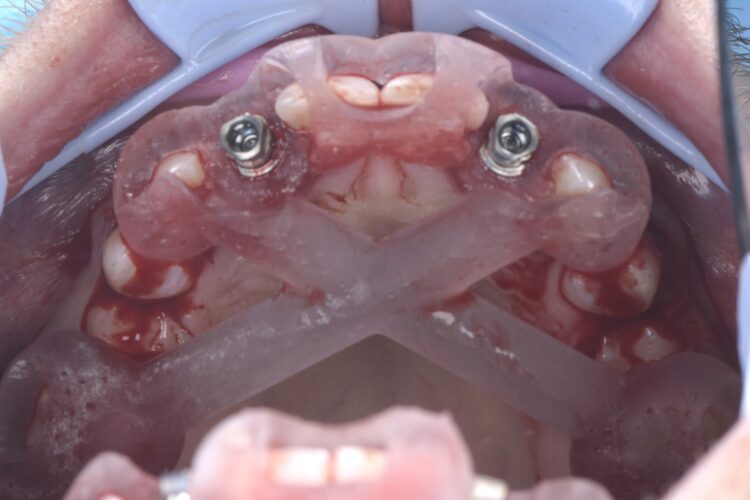

The implant surgery was performed in May 2023 and was filmed live as part of a surgical demonstration for the delegates on a guided surgery course being run by the Fitz Fahey Academy. Implants were placed in the UR2 and UL2 spaces with simultaneous hard and soft tissue grafting. Following the surgery, the patient was provided temporary teeth and instructed to avoid putting undue pressure on the implants during healing.